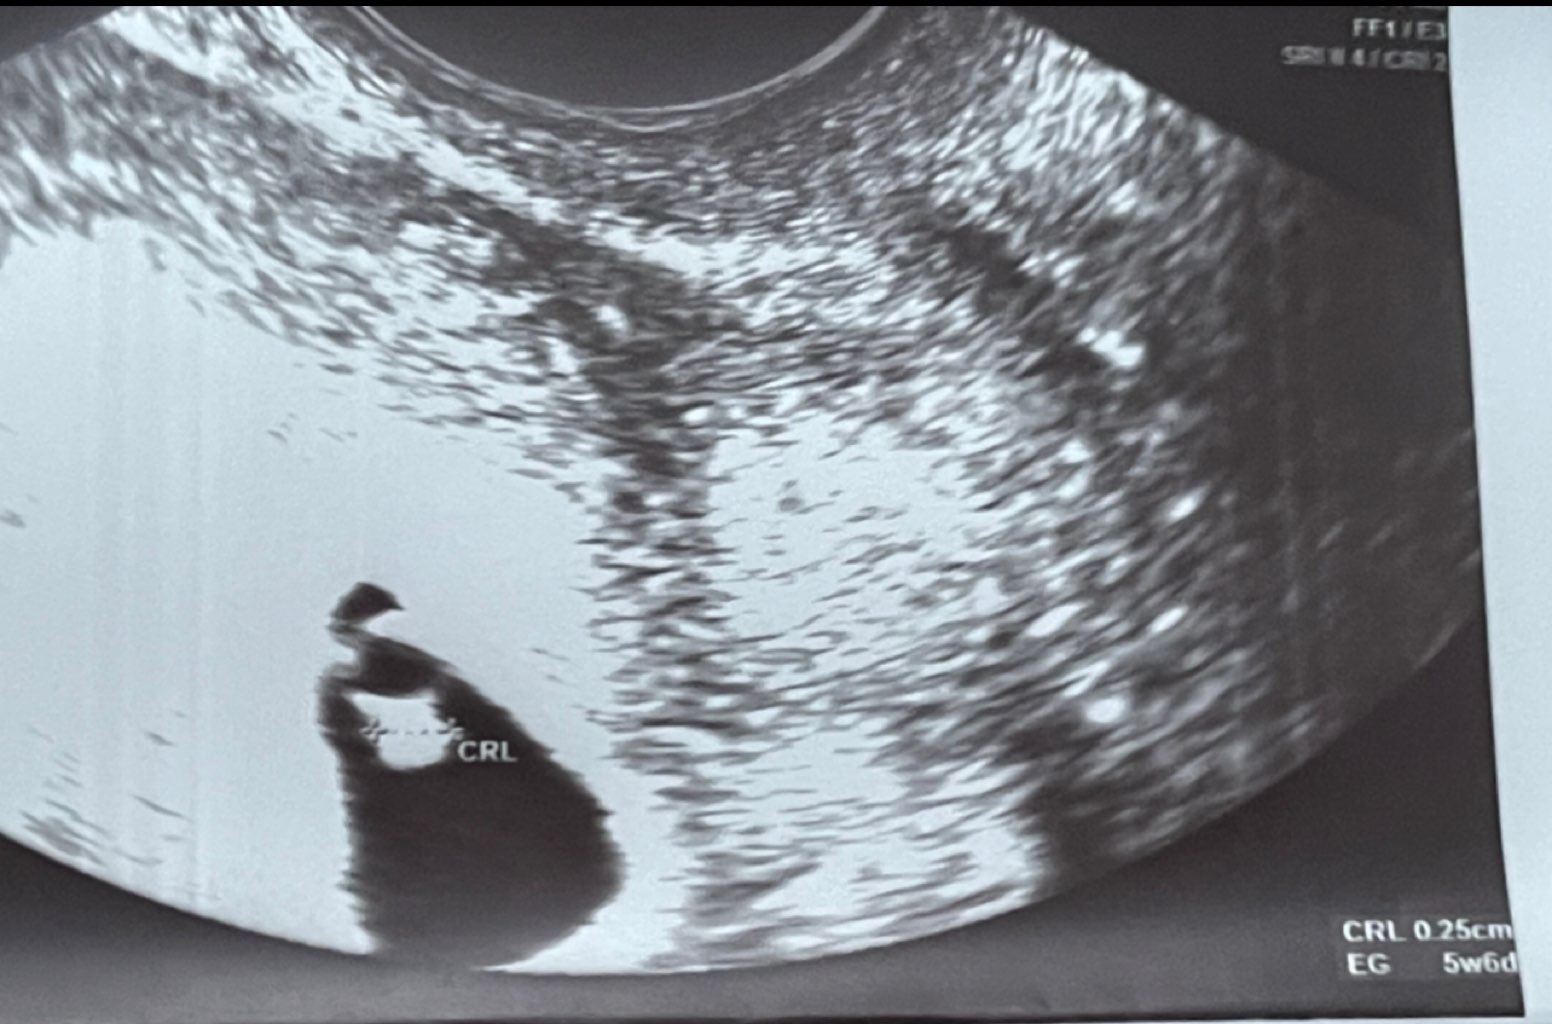

Powiedziała mi ze ciąża ma 5+6 - czyli tak jak ja cały czas powtarzałam, ze na 100% jest znacznie młodsza niż licząc od okresu (z okresu: 6+6!). Wiec jak usiadłam na ten fotel dzisiaj to nie chciałam patrzeć na ekran! Tak się bałam zobaczyć znowu puste jajeczko, jak mi zaczęła mówić „spójrz” a już mnie kojarzyła pielęgniarka to mówią, spójrz kto tam jest! No i wtedy płacz!